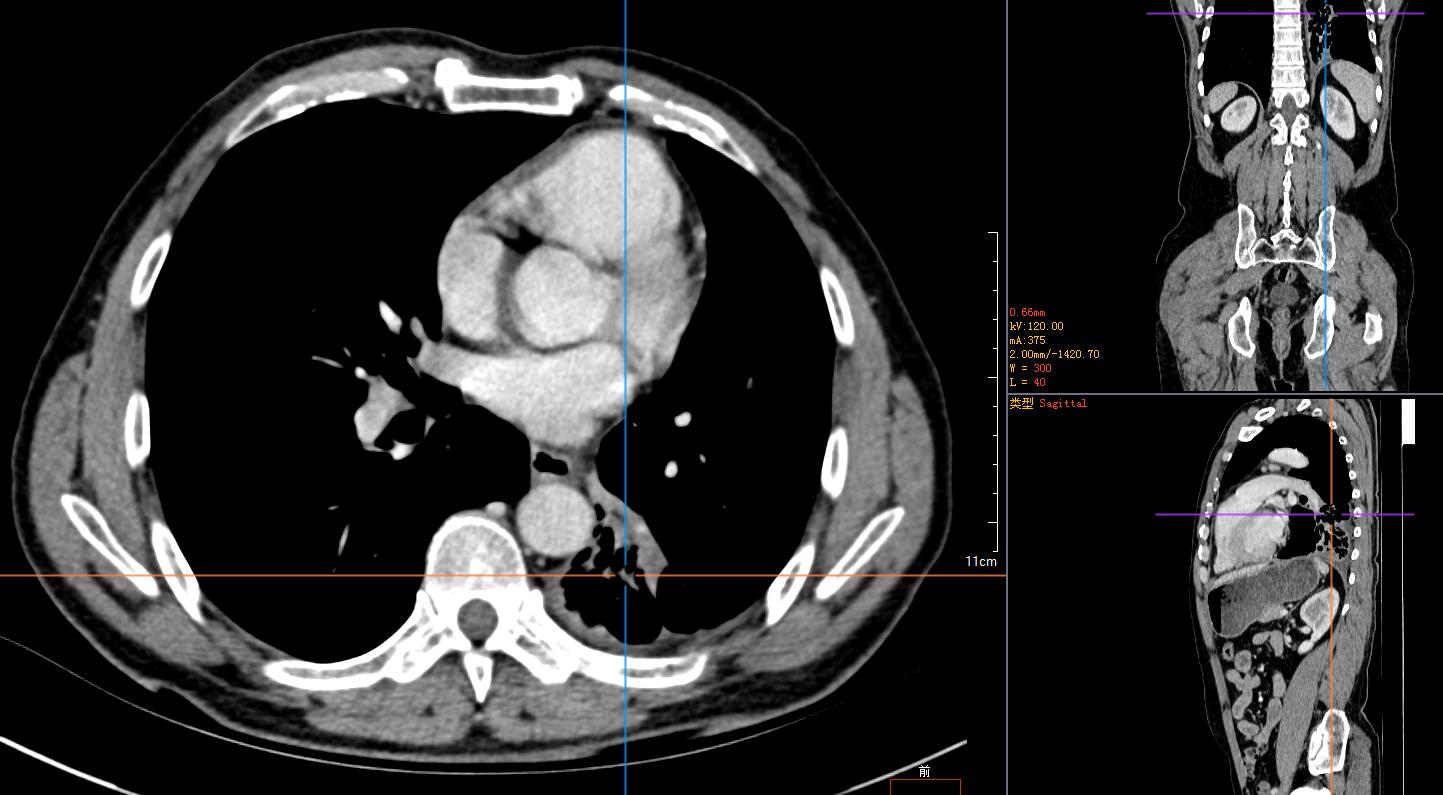

2)胸腹部平扫+增强CT示:左肺占位性肿块伴阻塞性肺不张,纵膈淋巴结肿大,建议穿刺活检。左肺动脉分支动脉瘤;右肾小错构瘤可能;双侧股骨颈小滑膜疝。